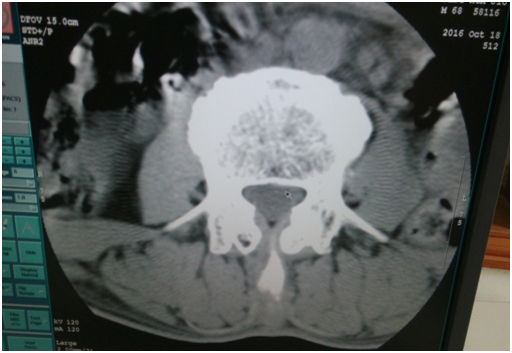

這是當(dāng)天做完這個(gè)圖像后,機(jī)器出現(xiàn)無法曝光。

2.     我用頭部條件掃水膜,可以曝光。但出來的圖像有環(huán)狀偽影,需要做校正。但是雙排的水膜在老區(qū),只能第二天再做校正。第二天做病人,做頭部的都還行,但是做腰椎圖像出來?xiàng)l紋狀偽影。

更換電源后,做校正。條紋狀偽影沒有了。

但是環(huán)狀偽影還是有。考慮到可能之前的校正文件有問題,做restore,導(dǎo)入之前好的校正文件。重新做校正,之后掃水膜圖像有明顯改善。